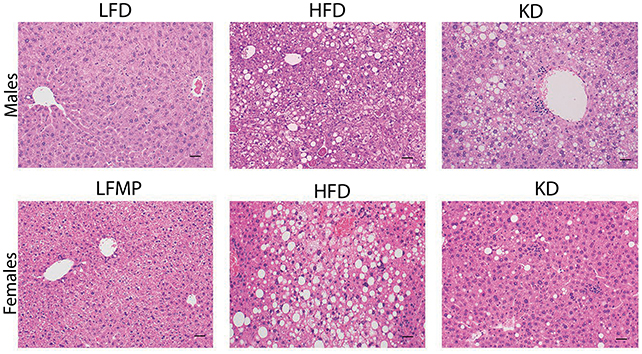

Within the scope of the contemporary investigation, researchers meticulously evaluated the physiological responses of mice maintained on four distinct dietary protocols for a minimum of nine months: a high-fat (Western-style) regimen; a highly fat-enriched, low-carbohydrate (keto-style) diet; a low-fat, high-carbohydrate diet; and a low-fat diet supplemented with protein levels comparable to the keto-style diet.

In contrast to the control group on a standard high-fat diet, the mice consuming the ketogenic diet exhibited a statistically significant lesser degree of weight gain. Nevertheless, the male subjects on the ketogenic diet developed fatty liver disease and manifested impaired hepatic function, indicative of metabolic disorders.

Both male and female mice on the ketogenic diet presented with suppressed levels of circulating glucose and insulin within a two-to-three-month timeframe. Subsequent analyses indicated that this phenomenon stemmed from a regulatory deficit, specifically inadequate insulin production by the pancreatic beta cells.

While further scientific inquiry is imperative to elucidate the underlying mechanisms and to ascertain the reasons for sex-specific hepatic complications, the research team posits that an excessive influx of circulating lipids may induce stress on pancreatic cells, thereby compromising insulin secretion.